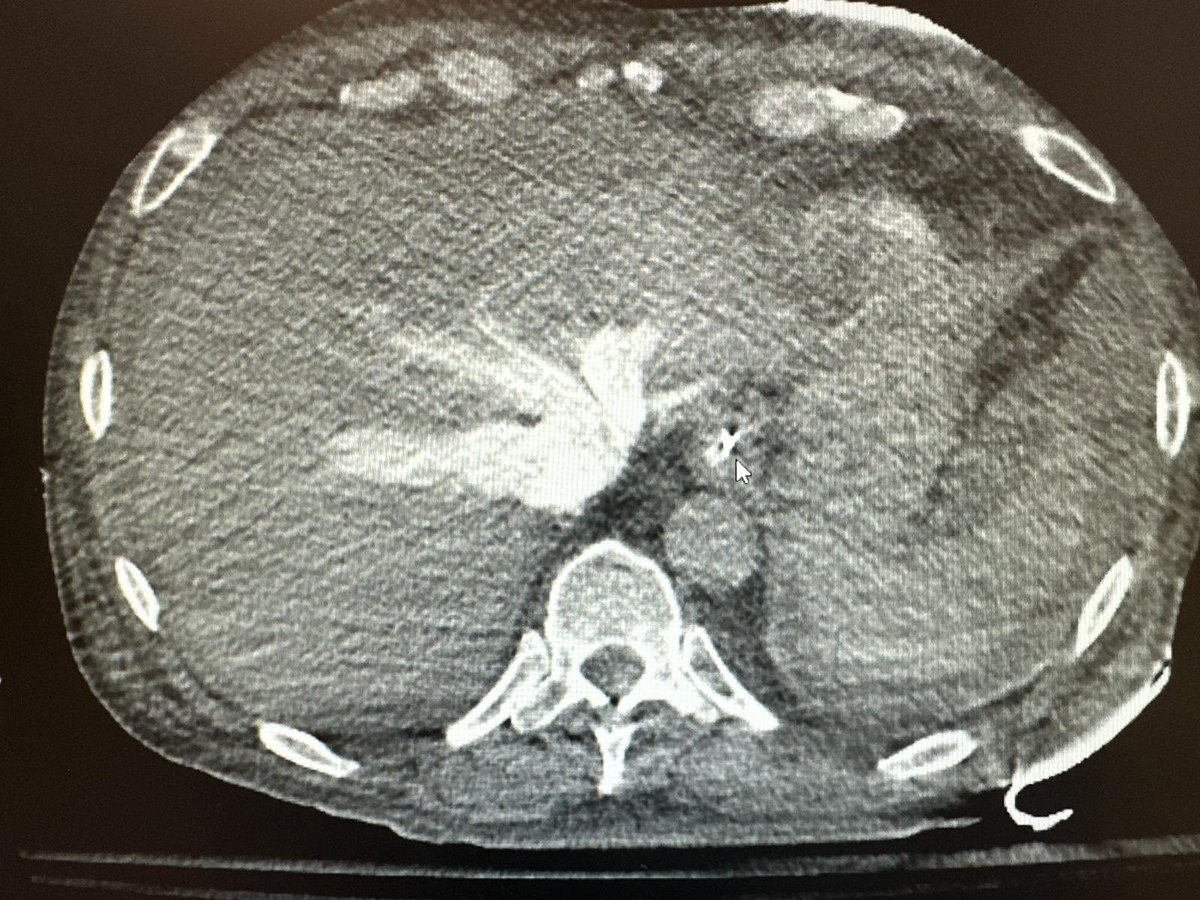

Pro tip: if a patient is sent for a CT PE protocol and this much contrast refluxes to the liver…you prob have cardiogenic/obstructive shock